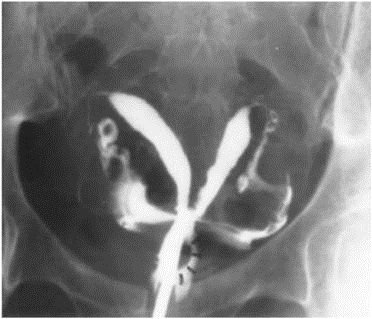

28歲G3P0的女性,因長期為經痛、經血過多(heavy menstrual bleeding)和性交疼痛所困擾,自述前三次懷孕都在12週內就自然流產,子宮輸卵管攝影(hysterosalpingography)影像如圖所示。建議接受子宮鏡 (hysteroscope)中膈切除手術,下列何者是手術後最可能改善的情況?

詳解

登入後即可查看逐題解析與答題